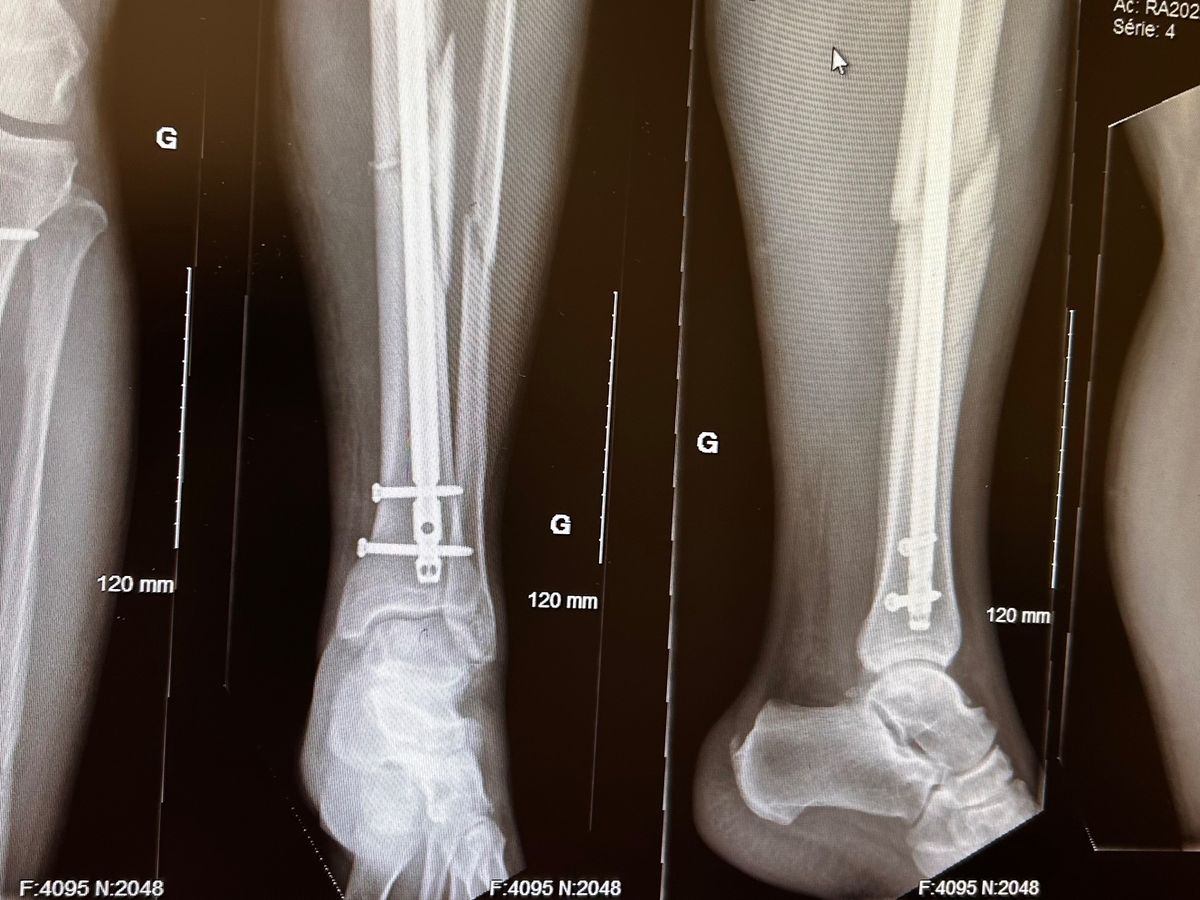

En ce qui concerne mon père, après avoir été transporter au centre hospitalier de Hull, les médecins ont déterminé que sa vie n'était pas en danger, mais il avait subi des fractures importantes au niveau de sa jambe gauche et de sa main droite. Le 10 octobre, les médecins l’ont opéré afin d’installer plusieurs vis et barre en métal pour reconstruire sa jambe. Depuis, la réhabilitation est incroyablement difficile, les centres hospitaliers étant débordés, mon père c’est retrouvé à la maison moins d’une semaine après l’opération. Cette semaine, nous avons eu la malheureuse nouvelle que le tout est à recommencer. Une nouvelle opération est prévue au courant de la semaine prochaine afin de retirer toute l’armature soutenant les os de sa jambe pour en réinstaller une nouvelle. La route vers la guérison sera longue et difficile, et toute la famille fait de son mieux pour passer au travers de ces étapes difficiles en se serrant les coudes. Mes sœurs et ma mère tiennent le fort comme des championnes depuis le début, et je prendrai l’avion dans deux semaines avec mon fils afin d’aller prêter main forte également.

As for my father, after being transported to the Hull hospital center, the doctors determined that his life was not in danger, but he had suffered major fractures in his left leg and right hand. On October 10, doctors operated on him to install several screws and metal rods to reconstruct his leg. Since then, rehabilitation has been arduous; with hospitals being overwhelmed, my father found himself at home less than a week after the operation. This week, we had the unfortunate news that the operation was unsuccessful, and it must be done all over again. A new operation is scheduled for next week to remove all the reinforcements supporting the bones of his leg so that they can reinstall new ones. The road to recovery will be long and difficult, and the whole family is doing their best to get through these difficult stages by sticking together. My sisters and my mother have held the fort like the amazing women that they are since the beginning, and I will be flying to Ottawa in two weeks with my son to lend a hand as well.